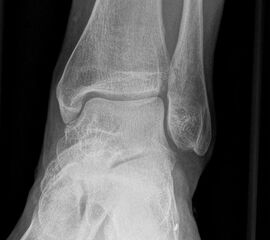

Sprunggelenk lateral ohne Belastung

Positionierung:

• Patient liegt auf dem Rücken und dreht den Fuß des aufzunehmenden Beins so nach innen, dass beide Malleolen genau übereinanderstehen.

• Die laterale Fuss-Seite liegt auf der Kassette, das Sprunggelenk ist 90° angewinkelt.

• Der Zentralstrahl wird zentral auf das Sprunggelenk gerichtet.

Kennzeichen des Röntgenbildes:

• Oberes und unteres Sprunggelenk sind rein seitlich abgebildet, inklusive Kalkaneus.

• Die Malleolen kommen übereinander zu liegen.

• Tibiagelenkfläche und Talusrolle werden exakt seitlich dargestellt, es kommt zu keinen Doppelkonturen.

• Die Fibula projiziert sich ins mittlere bis hintere Drittel der Tibiagelenkfläche.

• Die vordere und hintere Tibiakante, das Chopart-Gelenk und das Subtalargelenk kommen zur Darstellung.

• Das proximale Ende des Os metatarsale V ist mit abgebildet.

• Der Weichteilmantel (Achillessehne) ist erkennbar.

Besondere Bemerkungen zum Beispielbild:

• Patient mit anamnestisch chronischer OSG Instabilität.

• Ventral der Tibia findet sich ein abgebrochener Osteophyt.

Zur Vollansicht und zum Lesen der Bildbeschreibung bitte die Bilder anklicken.